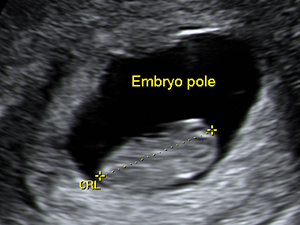

懷孕9週的胚胎頭臀長